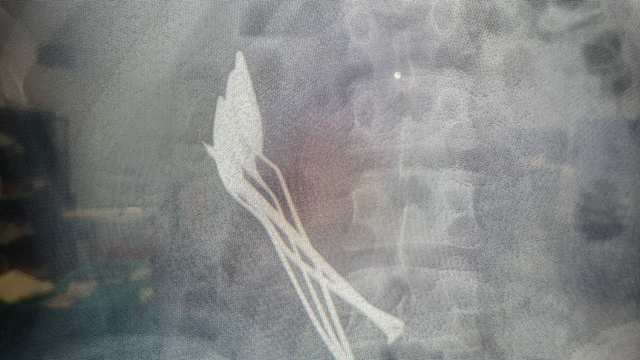

KAYSERİ'de 15 yaşındaki erkek çocuğunun midesinden, 2 saat süren operasyonla 4 metal tatlı kaşığı ve 1 çivi çıkarıldı.

Kentte, bir aile çocuklarının mide şikayeti üzerine hastaneye başvurdu. Kayseri Şehir Hastanesi’nde yapılan incelemede çocuğun midesinde 4 metal tatlı kaşığı ve 1 çivi görüldü. Kayseri Şehir Hastanesi Çocuk Cerrahisi ve Ürolojisi Anabilim Dalı Başkanı Doç. Dr. Mustafa Erman Dörterler ve ekibi tarafından yaklaşık 2 saat süren operasyonda çocuğun midesindeki kaşıklar ve çivi çıkarıldı. Erkek çocuğu tedavisinin ardından taburcu edildi.